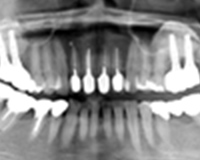

症例12歯がグラグラで食事が十分に出来ないケースを全体的にインプラントで治療したケースです。